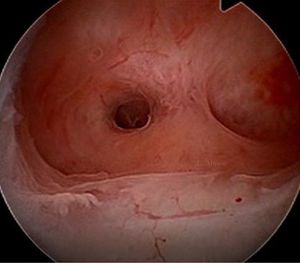

Adhesions originating in the myometrium are the most common type and are usually formed by muscular covered by endometrial tissue.